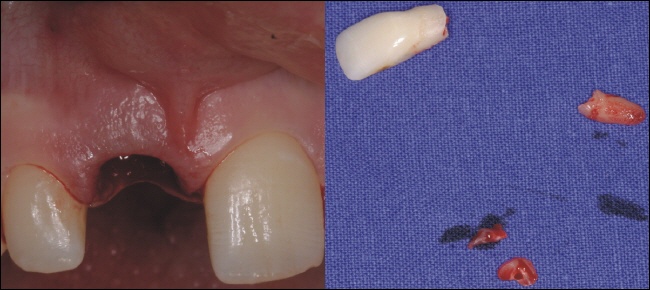

Zahnentfernung

Der Zahn ist durch seine Fraktur (Bruch) nicht zu erhalten und wird schonend entfernt. Auf dem rechten Bild sieht man die beiden Fragmente (Krone und Wurzelende), links die Situation direkt nach der Zahnentfernung.